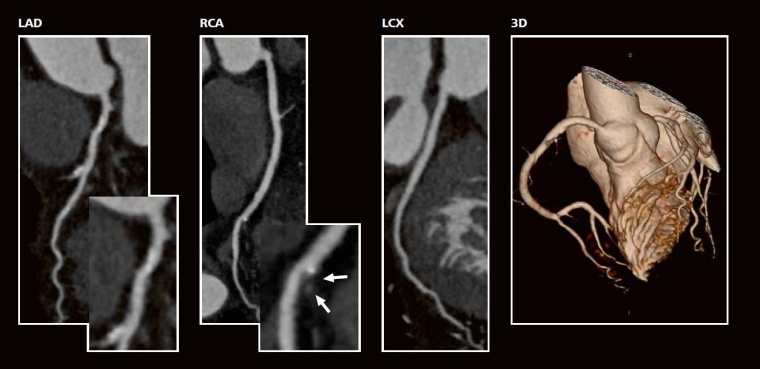

CT -Angiographie:

in der multiplanaren Rekonstruktion (Curved MPR) diskrete kalzifizierte und nicht-kalzifizierte Plaquebildung im proximalen RIVA (links), Ramus Diagonalis 1 (links) und in der mittleren RCA (Mitte, weiße Pfeile). Unauffällige LCX (rechts). Gesamt-Agatston-Score = 290 (mittleres Risiko). Keine relevanten Stenosen (3D-Bild). Strahlendosis CTA = 0,7 mSv.